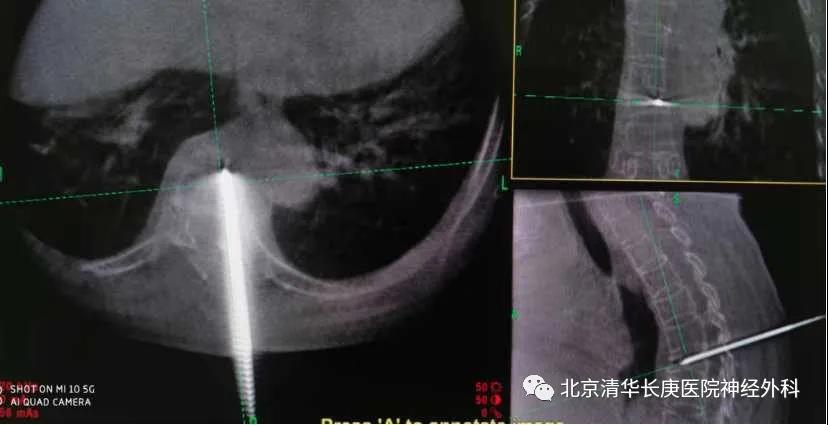

我院神经外科今天就为一名摔伤后椎体压缩骨折的病人进行了术中O-arm三维影像引导下的微创经皮穿刺椎体成形术。病人是一名65岁女性,摔伤后有严重的胸背部疼痛,伴腹部的局部放射,术前检查提示为胸7椎体压缩骨折。

图2 O-arm三维图像确认穿刺满意

据患者的主刀医生孙振兴介绍,椎体压缩骨折是老年人摔伤后常见的疾病,微创经皮穿刺椎体成形是目前主流的治疗方法。整个手术只需局部麻醉,无切口,手术后疼痛缓解迅速,1天内就可出院,O-arm等先进设备的使用有利于减少手术时间和射线,提高了手术效率和质量,克服了传统C臂透视的不足。